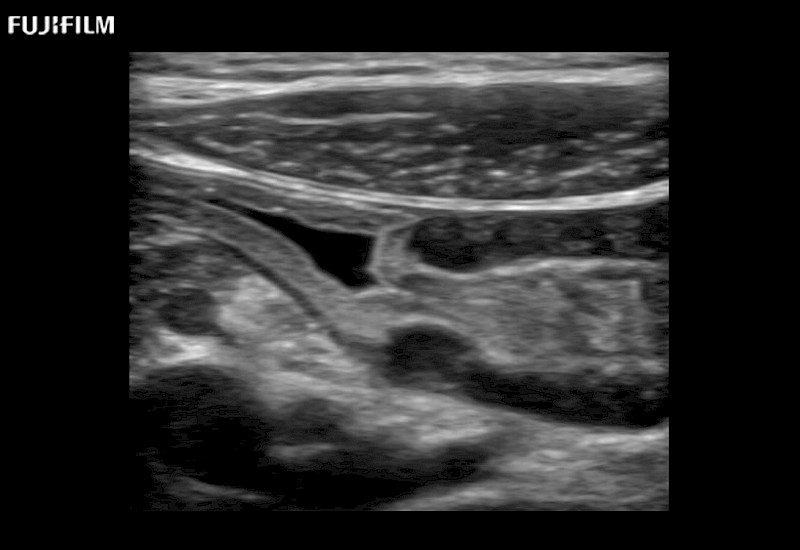

Curved array deep penetration “T” style finger-grip transducer for open surgical procedures.

Linear array side-fire “T” transducer for open surgical procedures.